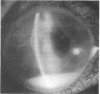

We have recently seen an unusual case of endophthalmitis secondary to Pasteurella multocida infection. Unlike previously reported cases this patient had no previous history of animal bites or scratch wounds. Treatment included subconjunctival, parenteral, and intravitreal administration of ampicillin. Although the eye was sterilised, the patient's vision remained poor owing to the extensive amount of retinal necrosis.